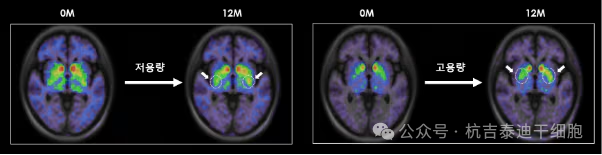

低剂量和高剂量TED-A9植入一年后的脑成像。

尤其是在干细胞治疗帕金森病植入一年后,对脑成像图像进行分析后发现,多巴胺转运蛋白的表达较植入前有所增加。干细胞治疗的开发者、延世大学医学院金东旭教授指出:“这表明干细胞在脑内存活,成熟为多巴胺神经细胞,并与周围区域和突触(神经细胞之间的连接)形成整合。”他补充道:“这可以被视为帕金森病中替换死亡多巴胺神经细胞的根本治疗机制的有力证据。”

研究将12名患者分为低剂量(315万细胞/侧)和高剂量(630万细胞/侧)组。结果显示,高剂量组在运动功能、日常活动能力方面的改善均显著优于低剂量组,清晰证明了疗效的剂量依赖性。PET影像显示,移植后患者大脑壳核区的多巴胺活性显著增强,且活性增强程度与临床症状改善直接相关,从影像学上印证了细胞的成功定植与功能整合。